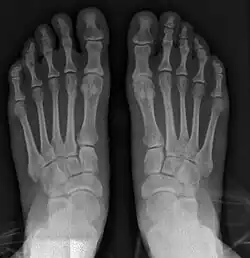

For recurrence correction after fusion procedure (Fig. 9) Metatarsus primus varus deformity and pain recurred 6 months after modified Lapidus procedure and it could also be again corrected by the syndesmosis procedure.